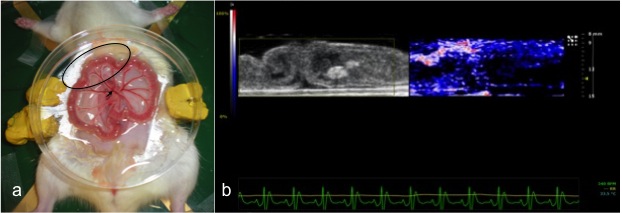

Photoacoustic imaging is an emerging modality that exploits the photoacoustic effect to combine the high contrast of optical imaging with the spatial resolution and penetration depth of ultrasound. A key feature of PA imaging methods is that they exploit optical contrast but employ US detection principles. The PA effect offers a way to take advantage of the ability of light to penetrate into the body and let us defeat light diffusion by using US waves to see the penetrating light. The main advantage of this hybrid approach is that the optical properties of biological tissue, including high contrast and spectral specificity, are encoded in an ultrasound signal. Resolutions of better than 1 mm can be obtained at depths measured in centimeters (up to 7) and not in millimeters, depending on the laser wavelength and transducer frequency used, opening up entirely new regimens of optical imaging. From a clinical standpoint, PA imaging is complementary in nature and synergetic with US and a combined US and PA imaging system can be easily implemented due to the presence of a shared detector and associated electronics. Furthermore, such a system will be readily accepted by clinicians familiar with US imaging.